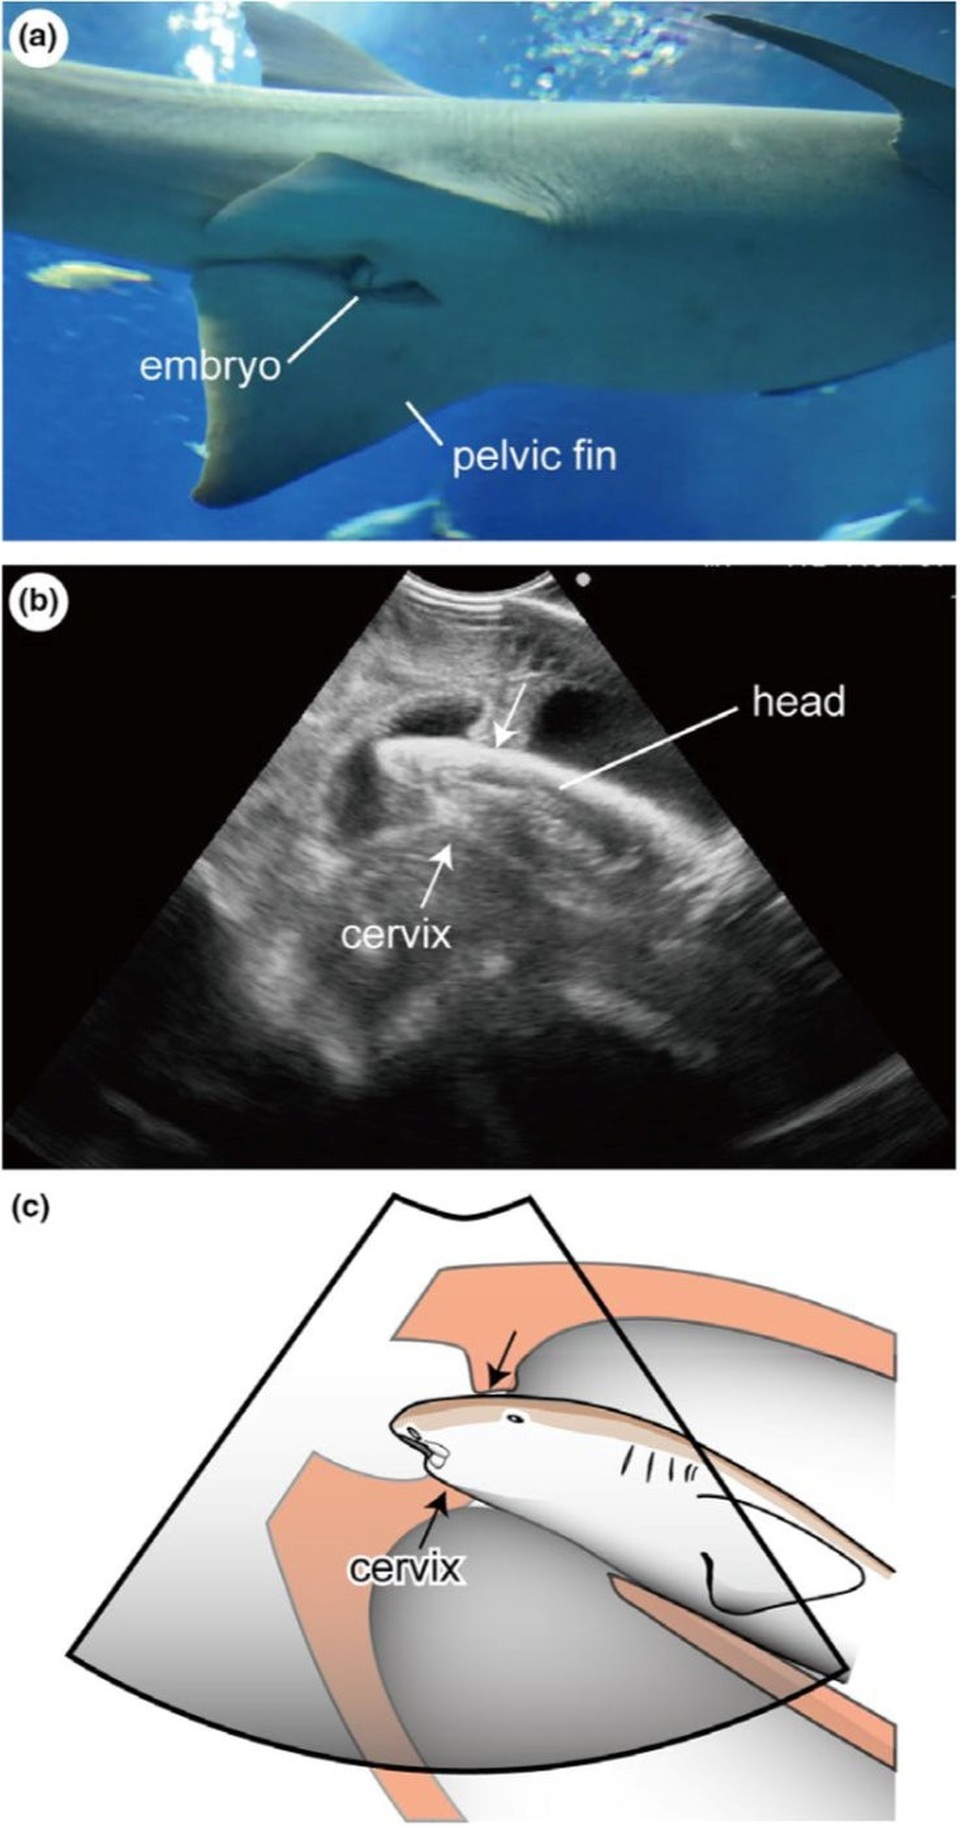

Và còn một điều thú vị nữa về loài cá này: phôi đôi khi ló đầu ra khỏi cổ tử cung.

Quan sát thực tế và siêu âm cho thấy cá mập con thò đầu khỏi tử cung mẹ.

Nói cách khác, đôi khi cá mập y tá hung con - dù chưa được sinh ra - vẫn ló đầu khỏi bụng mẹ để quan sát thế giới bên ngoài. Hiện tượng này khác hẳn với các loài động vật có vú, tử cung của chúng luôn đóng chặt và chỉ mở ra khi sinh nở.